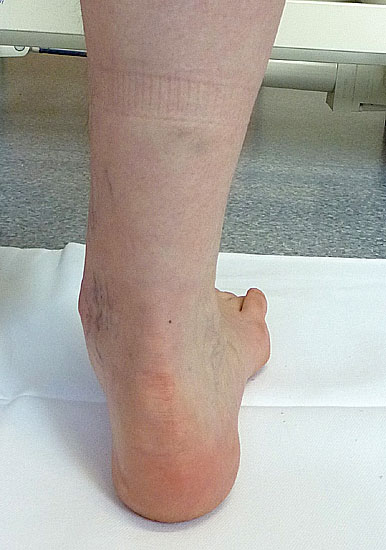

• von hinten

• Morphologie der Beinmuskeln (Seitendifferenz, Waden distal dünn (Abb. 11), Narben)